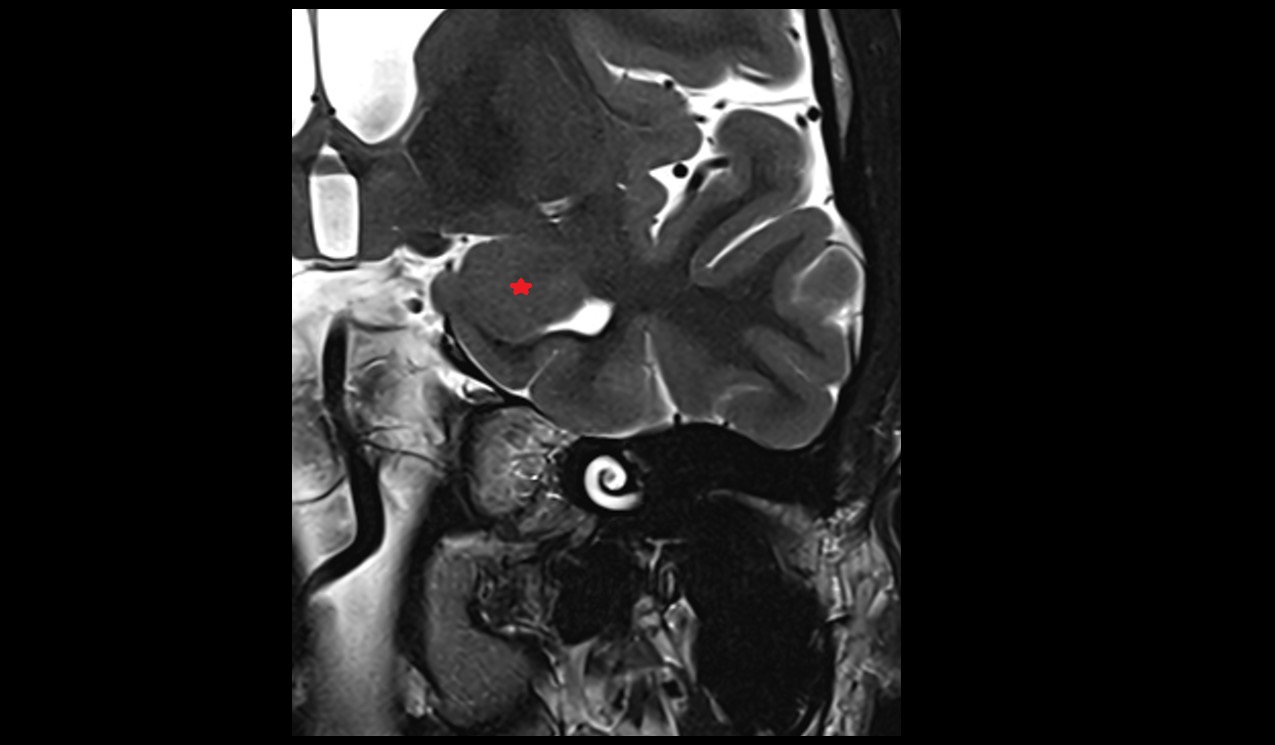

- Cerebellar tonsil (H IX)

- Tonsil of cerebellum